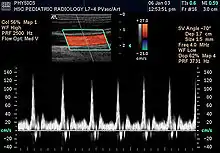

Спектральная доплерография

Предназначена для оценки движения подвижных сред. В частности, кровотока в относительно крупных сосудах и камерах сердца, стенок сердца. Основным видом диагностической информации является спектрографическая запись, представляющая собой развертку скорости кровотока во времени. На таком графике по вертикальной оси откладывается скорость, а по горизонтальной — время. Сигналы, отображающиеся выше горизонтальной оси, идут от потока крови, направленного к датчику, ниже этой оси — от датчика. Помимо скорости и направления кровотока, по виду доплеровской спектрограммы можно определить характер потока крови: ламинарный поток отображается в виде узкой кривой с четкими контурами, турбулентный — широкой неоднородной кривой.

Импульсная СД

Методика базируется на периодическом излучении серий импульсов ультразвуковых волн, которые, отразившись от эритроцитов, последовательно воспринимаются тем же датчиком. В этом режиме фиксируются сигналы, отраженные только с определённого расстояния от датчика, которые устанавливаются по усмотрению врача. Место исследования кровотока называют контрольным объёмом. Достоинства: возможность оценки кровотока в любой заданной точке.